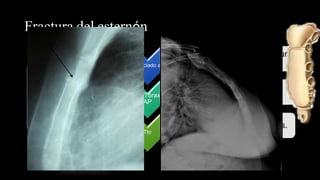

Fractura del esternón

DX:

Antecedente

de trauma,

dolor en

área pre-

esternal.

Confirmar:

RX de tórax

en

proyección

lateral.

Asociado a

• Contusiones cardíacas, ruptura

aorta y traqueobronquiales.

Rx Tórax

AP

• Imagen de hemomediastino.

Tto

• 1)Analgesia. 2) Osteosíntesis.